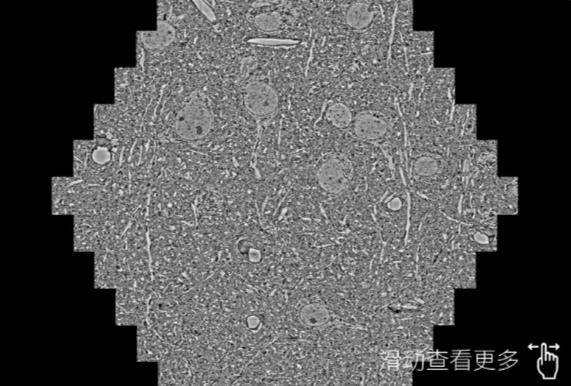

鼠脑切片。左图使用海南蔡司海南扫描电镜MultiSEM706对165μmx143pm面积区域成像,耗时仅需1.5秒。右图为鼠脑切片中30μm区域放大效果。样品由芝加哥大学B.Kasthuri提供。

使用蔡司高速海南扫描电镜MultiSEM对1mm²人脑皮层组织进行高分辨成像,并对其中的各种细胞结构进行三维重构分析。左图展示了2x3mm²组织平面中锥体神经元的三维重构效果。右图显示了局部体积神经元三维重构。图像由哈佛大学chtman实验室提供,渲染图由D. Berger 制作。